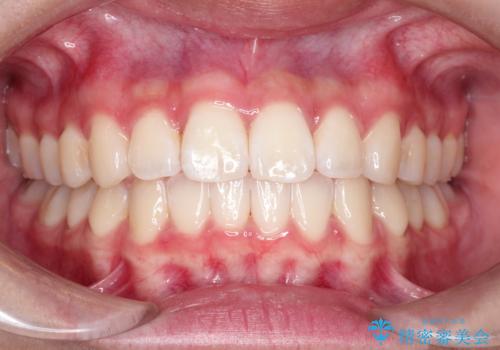

前歯のねじれを改善 小矯正+マウスピース矯正インビザライン

前歯の重なりは奥歯のズレが原因:まとめてインビザラインで治す